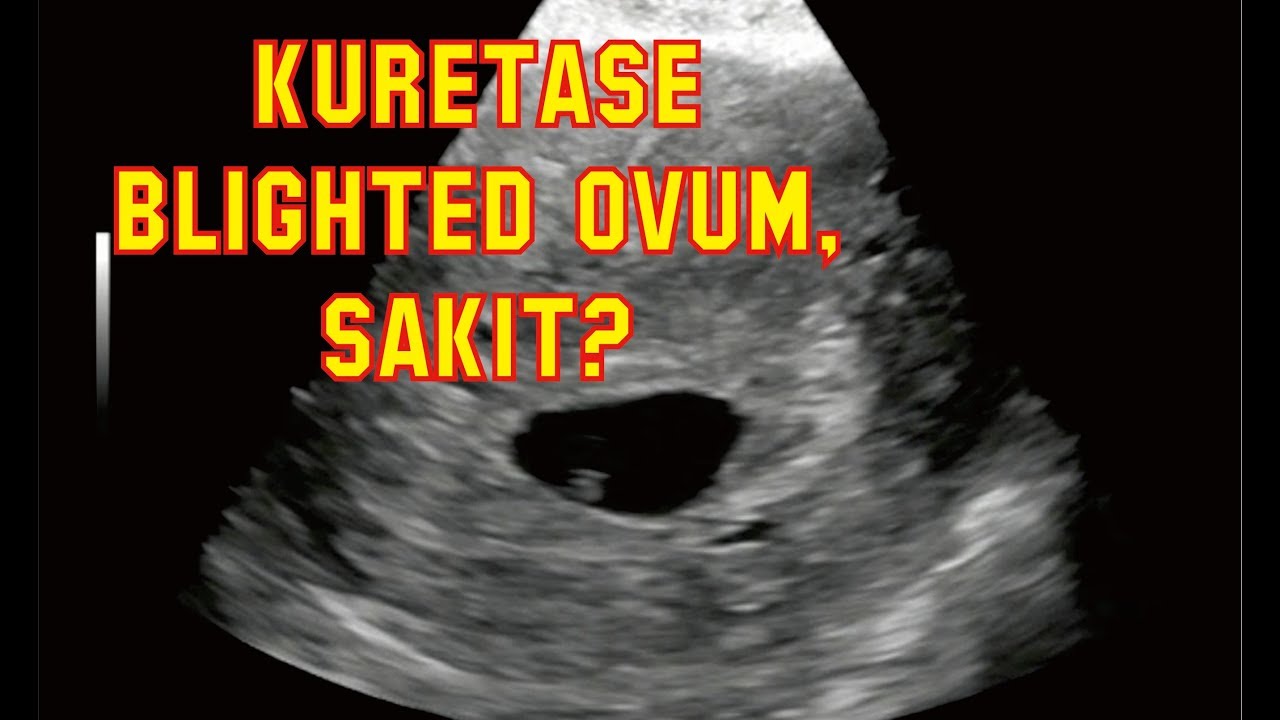

KURETASE BLIGHTED OVUM (HAMIL KOSONG) – Pengalaman – Dijah Arif - YouTube

KURETASE BLIGHTED OVUM (HAMIL KOSONG) – Pengalaman – Dijah Arif - YouTube